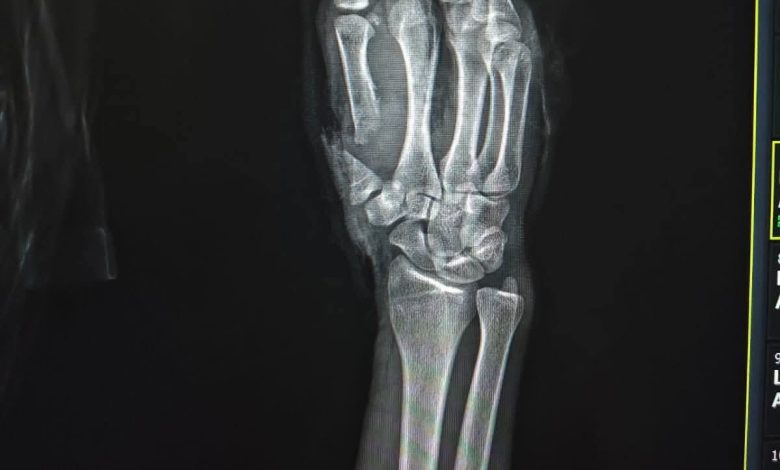

وأوضح البيان أن الفريق الطبي أجرى جراحة ميكروسكوبية دقيقة استمرت نحو 6 ساعات، تم خلالها إعادة توصيل الشرايين والأوردة والأعصاب، إلى جانب تثبيت العظام، بما أسهم في إنقاذ الإصبع واستعادة وظيفته الحيوية.